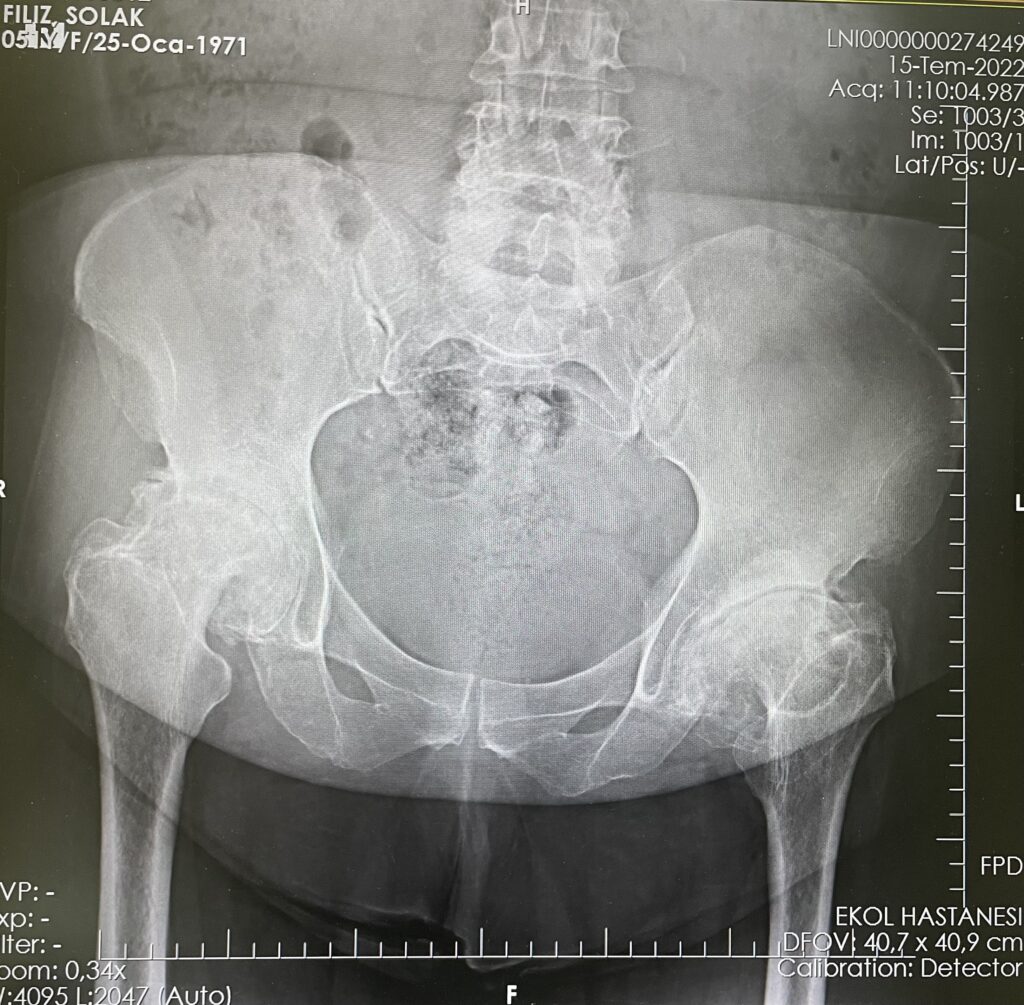

F.S.